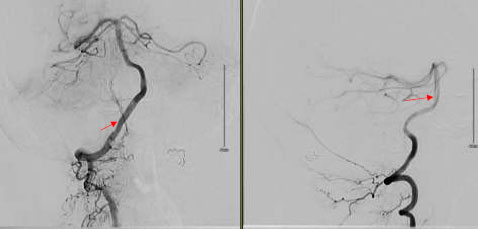

The patient, who presented with transient episodes of focal neurological deficits for six months, is a Caucasian female in her late 50s with a medical history of Hypertension and Diabetes. These episodes were wake-up weakness, confusion, and dysarthria on the right side of the body. She was prescribed Aspirin by a local neurologist. The episodes became more severe as she would have transient quadriparesis, dizziness, and aphasia lasting for several hours. These symptoms would happen particularly in the right lateral position. Her neurological exam was completely normal. CT scan head was normal, while CT Angiography revealed increased tortuosity of the V4 segments of the vertebral arteries and the basilar artery. These were indenting the Medulla oblongata. MRI brain confirmed similar findings (Fig. 1). A conventional angiogram was done, which revealed compression of the medullary pyramid on the left side due to dilated proximal basilar artery associated with significant vertebrobasilar atherosclerotic plaques (Fig. 2). No rate-limiting changes in flow were observed while turning the head to either side during the procedure, but approximately 50% flow arrest was seen in the right vertebral artery on turning the patient’s head to the right.

Cerebral angiography is the gold standard for the diagnosis of VBD. It can also help in deciding medical treatments versus endovascular intervention. Angiography was helpful in our case as it helped to quantify the severity of VBD. We were also able to rule out bow-hunter syndrome. Bow hunter syndrome results from mechanical compression of vertebrobasilar circulation on rotation or extension of the neck [17]. Due to significant atherosclerotic plaques seen in our patient, we managed her conservatively with dual antiplatelet therapy. Current evidence on the use of antiplatelet agents is limited to case series and anecdotal reports. In one of the case series, 79 out of 156 subjects were treated with antiplatelet agents, with a 1-year cumulative risk of stroke of 42% despite treatment [4].